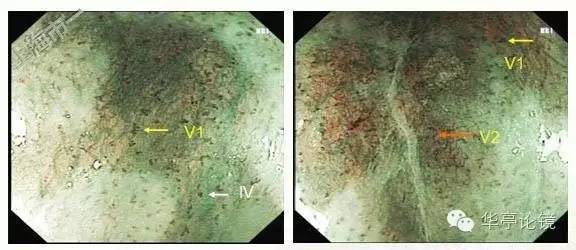

ME-NBI内镜:见多处病灶粘膜血管网异常,分支血管网缺失,局部背景着色阳性,IPCL呈IV-V1型改变为主(注:IV型: 出现扩张、迂曲、管径粗细不均或形态不规则改变中的2种或3种;V型:同时出现扩张、迂曲、管径粗细不均和形态不规则四种改变),局部见V2型改变(注:Ⅴ2型:在Ⅴ1型病变的基础上出现血管延长,原血管袢结构尚完整)。预测病变深度为m1(上皮层)为主,见下图。本文IPCL分型均按井上分型方法。